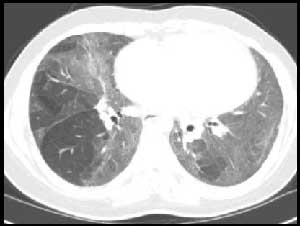

风湿性疾病肺受累常见影像学表现

类风湿结节